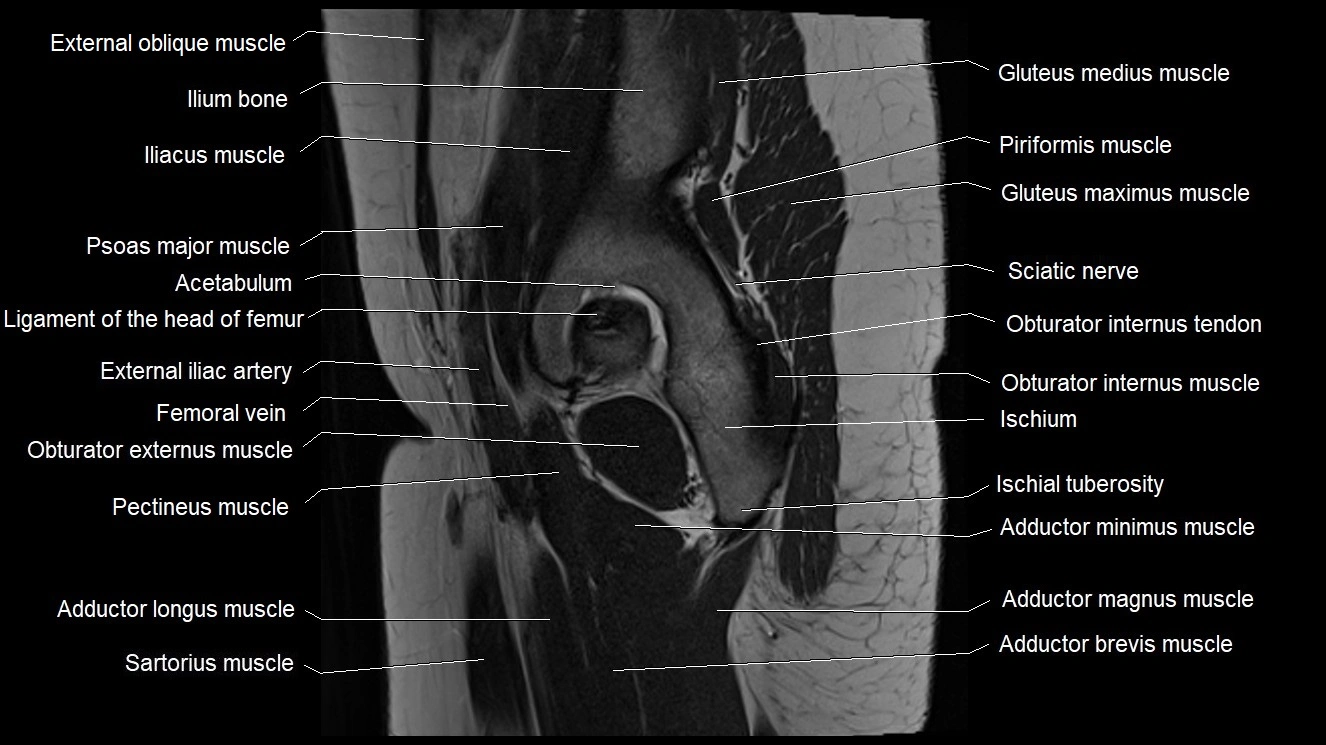

- Adductor brevis muscle

- Adductor longus muscle

- Adductor magnus muscle

- Adductor minimus muscle

- External iliac artery

- Femoral vein

- Gluteus maximus muscle

- Gluteus medius muscle

- Gluteus minimus muscle

- Gracilis muscle

- Ilium bone

- Ischial tuberosity

- Ischium bone

- Obturator externus muscle

- Obturator internus muscle

- Obturator internus tendon

- Pectineus muscle

- Psoas major muscle

- Sartorius muscle

- Vastus lateralis muscle